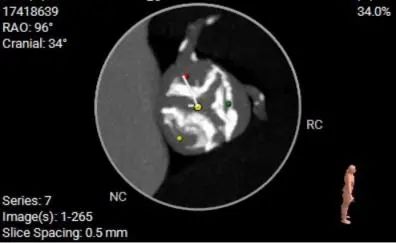

主动脉根部评估

ANNULUS

LVOT

SOV DIAMETER

STJ

ASCENDING AORTA

LEFT VENTRICLE

冠脉开口高度

LEFT CORONARY

左冠开口高度14.7mm

RIGHT CORONARY

右冠开口高26.9mm

左冠脉风险评估

右冠脉风险评估

钙化分布:HU850:852.2m³